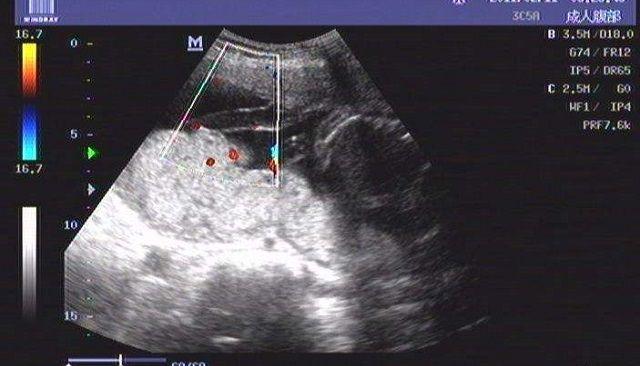

赴泰后,专家先是根据女性的实际情况制定专属的促排方案,然后使用经过泰国FDA监管认证的天然无副作用药物进行促排;用药期间通过多次B超监测卵泡发育情况,并抽血检查女性对药物的反应程度,以此调整用药剂量,确保女性身体健康,同时获得理想的促排效果;待卵泡发育成熟,专家便会注射破卵针(HCG/Lupron),于36小时后进行无痛取卵。